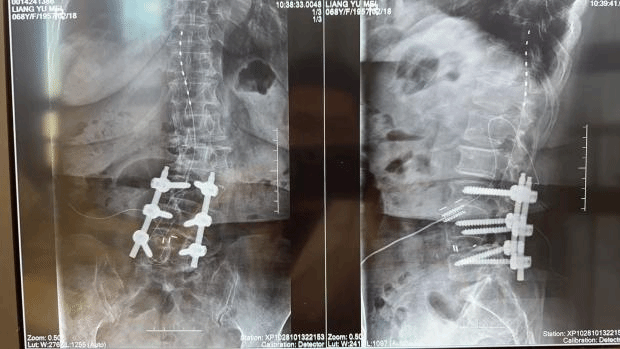

术前,团队借助影像学精准定位疼痛靶点,制定了个性化手术规划。术中在局部麻醉下,仅通过两个不足0.5厘米的微小切口,将电极精准植入脊髓硬膜外腔。手术全程耗时约1小时,通过实时神经电生理监测与患者术中反馈,确保电极位置精准无误,避免损伤周围神经血管。

术后,患者即刻反馈腰痛与右下肢疼痛明显缓解,困扰她一年多的顽痛大幅减轻。在医护人员指导下,患者当天即可下地行走,且行走姿态恢复正常,彻底摆脱了疼痛的束缚。目前,患者恢复良好,疼痛评分已降至正常范围,正在进行后续康复随访。